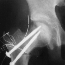

- To determine the osteotomy plane, two K-wires are placed through

the denuded surface of the greater trochanter both anterioly and

posterioly in a plane perpendicular to the another K-wire which

is placed along the femoral neck.

- Two large pins are inserted parallel into proximal and distal

fragments, and femoral head is rotated anteriorly by handling

proximal pin.

- After adequate rotation, a large screw is inserted in valgus

position. An A-P X-ray should be taken to ensure the weight-bearing

portion is well apposed and the neck-shaft angle. Then a Steinman

pin is removed and another large pin is inserted. The A-O compression

screw is ineffective because of its thin shank.